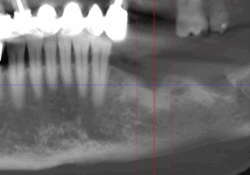

Reprise de traitement implantaire

La reprise de traitement désigne le processus par lequel un patient reprend des soins après un échec de traitement implantaire ou lorsque des complications surviennent. Voici les étapes typiques d’une reprise :

En cas d’échec ou de complications, la reprise de traitement implique une évaluation diagnostique, une extraction (si nécessaire), une cicatrisation, puis une reconstruction osseuse suivie d’une nouvelle implantation.